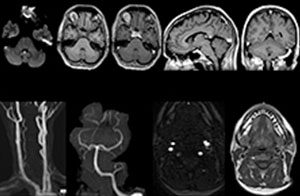

When neurological emergencies require diagnostic imaging, common practice in the ED has been to perform CT rather than MRI, even when MRI could potentially produce more informative diagnostic images of spinal cord damage, disc protrusions, soft tissue injuries, and stroke pre-cursors. [1,2] The main reason is that timing is essential in emergency cases, and CT is generally faster than MRI. The St. Joseph’s Hospital and Medical Center is now challenging this paradigm by offering rapid MRI scans within its Neurologic ED and seeing that it helps them make a richer diagnosis.

To minimize the time taken to perform scans, rapid MRI examination protocols (ExamCards) were developed, shortening the total scanning time to even less than 10 minutes in some exams. Techniques like mDIXON (modified DIXON) are used for robust capturing of fat-free MRI images in a hectic ED environment.

“For the thoracic and cervical spine routine non-contrast exam, for example, we perform one mDIXON T2 TSE sequence, which provides us with two outputs: the fat-and-water-together T2-weighted images, as well as the water-only sagittal T2-weighted images. And then we also perform an axial gradient echo exam.”

A range of protocol sheets was developed to help ensure that referring physicians order the most appropriate MRI exam. The optimized MRI protocols also include 3D contrast-enhanced imaging, allowing neurosurgeons to comfortably use the isotropic data in the operating room while performing stereotaxic surgery.